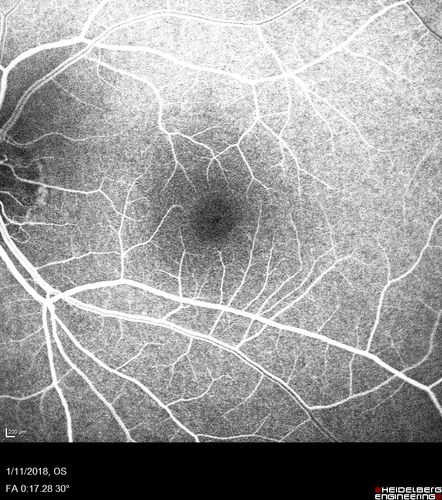

Foveal Red Spot Syndrome Left Eye

She noticed on covering the right eye that she had distortion off center in the left eye a few weeks ago.  She had a temporal paracentral scotoma intermittently visible on the eye examination.  She does notice that the left eye is not as good as the right eye now that it has been brought to her attention.  She has every now and then a little twitch in the left eye.  She has no pain on eye motion.

VA OD: sc20/20 NccJ1+

VA OS: sc20/20-1